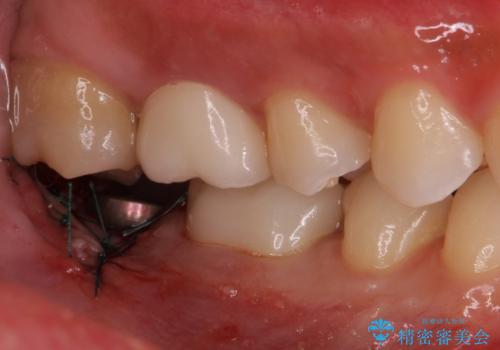

インプラント入れて噛めるようにしたいとのことだったため、治療を行います。

向かい合わせになる歯が歯茎と噛んでいるため、歯茎の厚みも調整していきます。

- 右下7/インプラント242,000円+アバットメント110,000円+インプラント用仮歯22,000円+ジルコニアクラウン(スタンダード)121,000円 合計495,000円(税込)費用は治療当時の料金となります

今回はかぶせ物の高さを確保するために、少し顎骨を削り、歯肉の厚みも薄くしました。